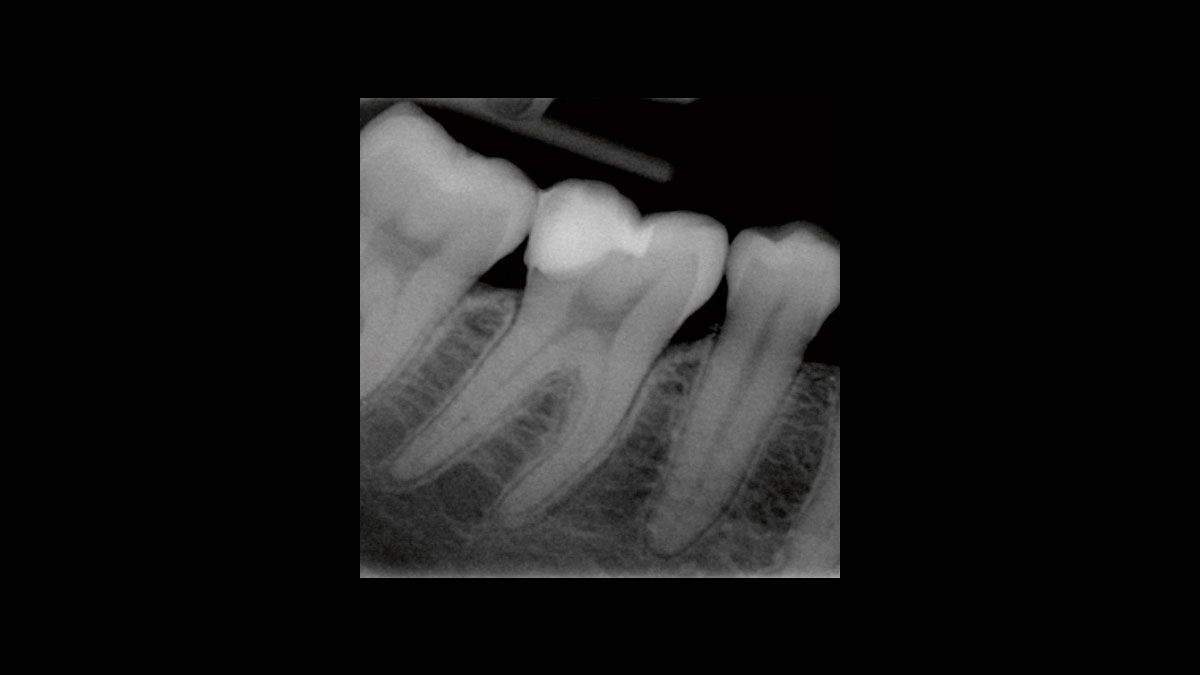

Réduction des germes endodontiques